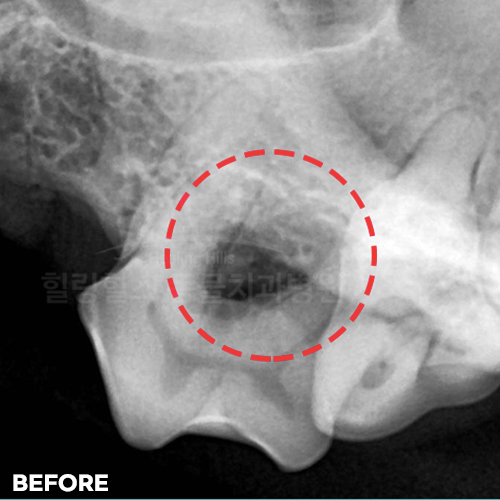

[치주염 치료 후 자라난 잇몸뼈]